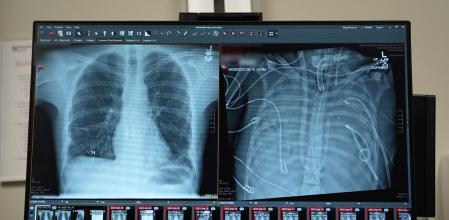

Radiografia del pacient sense pulmons connectat al sistema artificial (dr.) I un cop transplantat (esq.)